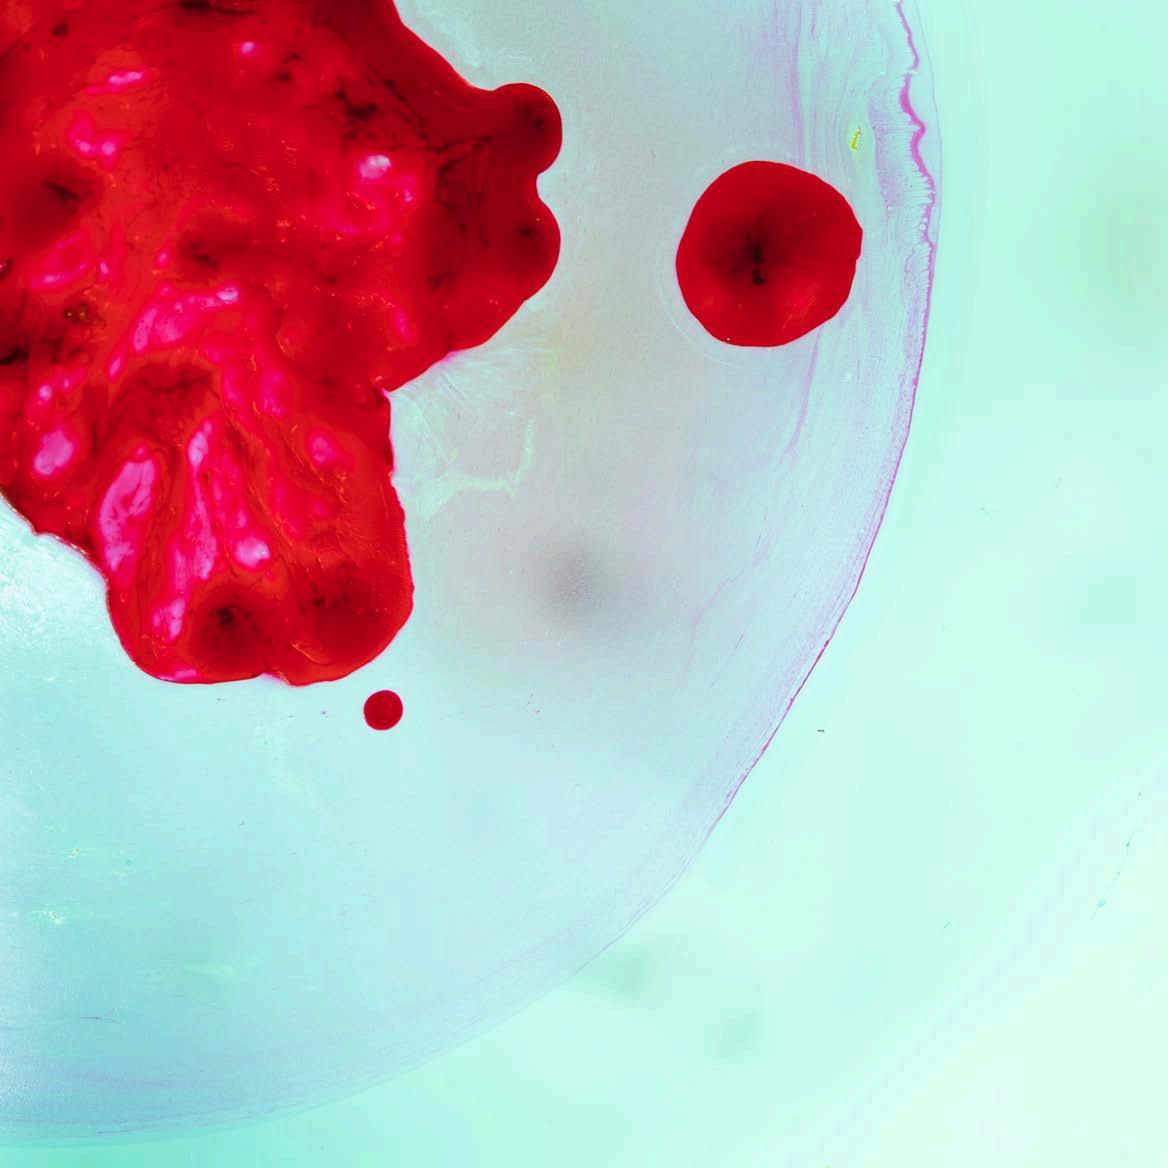

A DREPANOCITOSE, TAMBÉM CONHECIDA COMO ANEMIA FALCIFORME, É UMA DOENÇA GENÉTICA HEREDITÁRIA QUE AFETA A HEMOGLOBINA NO INTERIOR DOS GLÓBULOS VERMELHOS. ESTA É UMA DOENÇA RARA NO NOSSO PAÍS E CONTINENTE. NA EUROPA, AFETA CERCA DE 40.000 PESSOAS E, EM PORTUGAL, HÁ 850 DOENTES DIAGNOSTICADOS.

A anemia falciforme ou Drepanocitose, outro nome pelo qual também é conhecida, é uma doença hereditária do sangue.

Anemia: é a complicação mais comum. Os glóbulos vermelhos com mutação "morrem" prematuramente e, por isso, não há glóbulos vermelhos suficientes para transportar oxigénio para todas as partes do corpo. Esta situação causa cansaço e falta de ar.